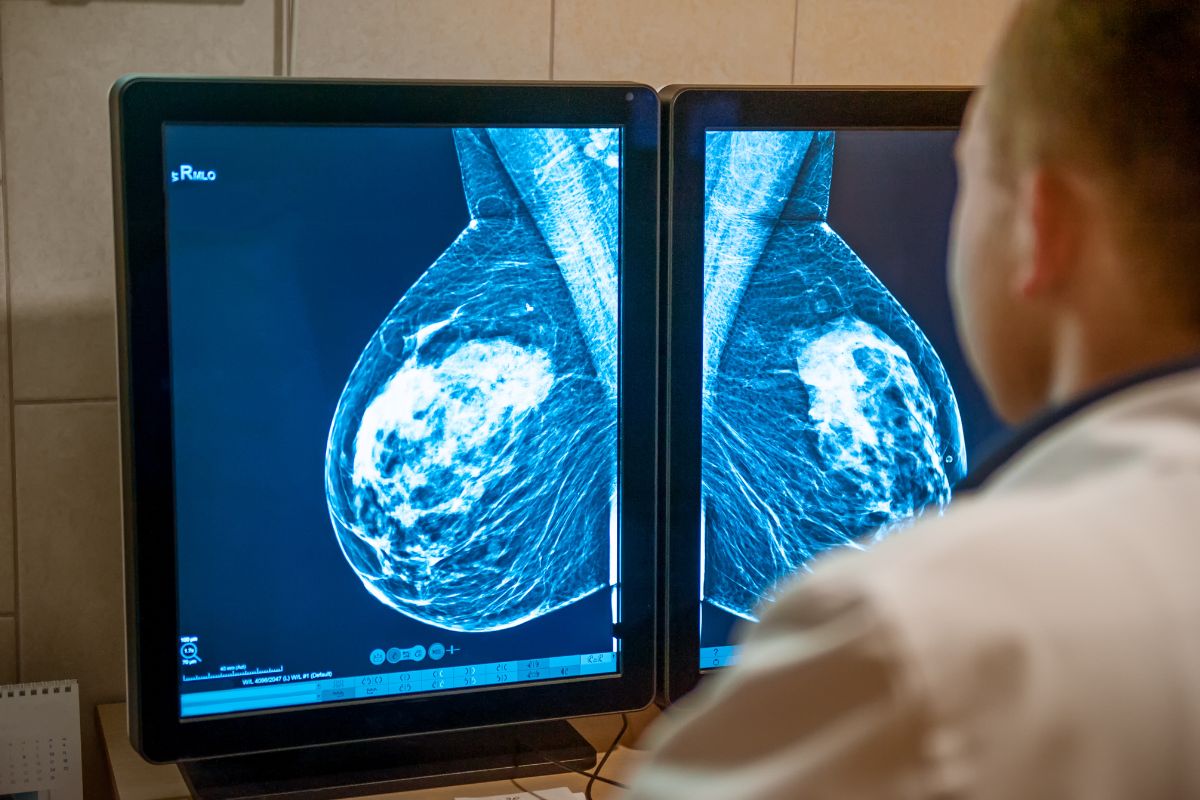

En un avance significativo en la lucha contra el cáncer de mama, investigadores han descubierto que la inteligencia artificial (IA) puede detectar señales de la enfermedad en mamografías hasta seis años antes de que se realice un diagnóstico clínico. Este hallazgo, publicado en la revista JAMA Network Open, promete revolucionar los programas de detección temprana y mejorar drásticamente las tasas de supervivencia.

El estudio, llevado a cabo en Noruega, analizó 116.495 mujeres que se sometieron a tres o más rondas consecutivas de mamografías de detección cada dos años entre 2004 y 2018. Los investigadores utilizaron INSIGHT MMG, un algoritmo de IA comercialmente disponible, para analizar las mamografías y generar un «puntaje de detección de cáncer» para cada imagen.